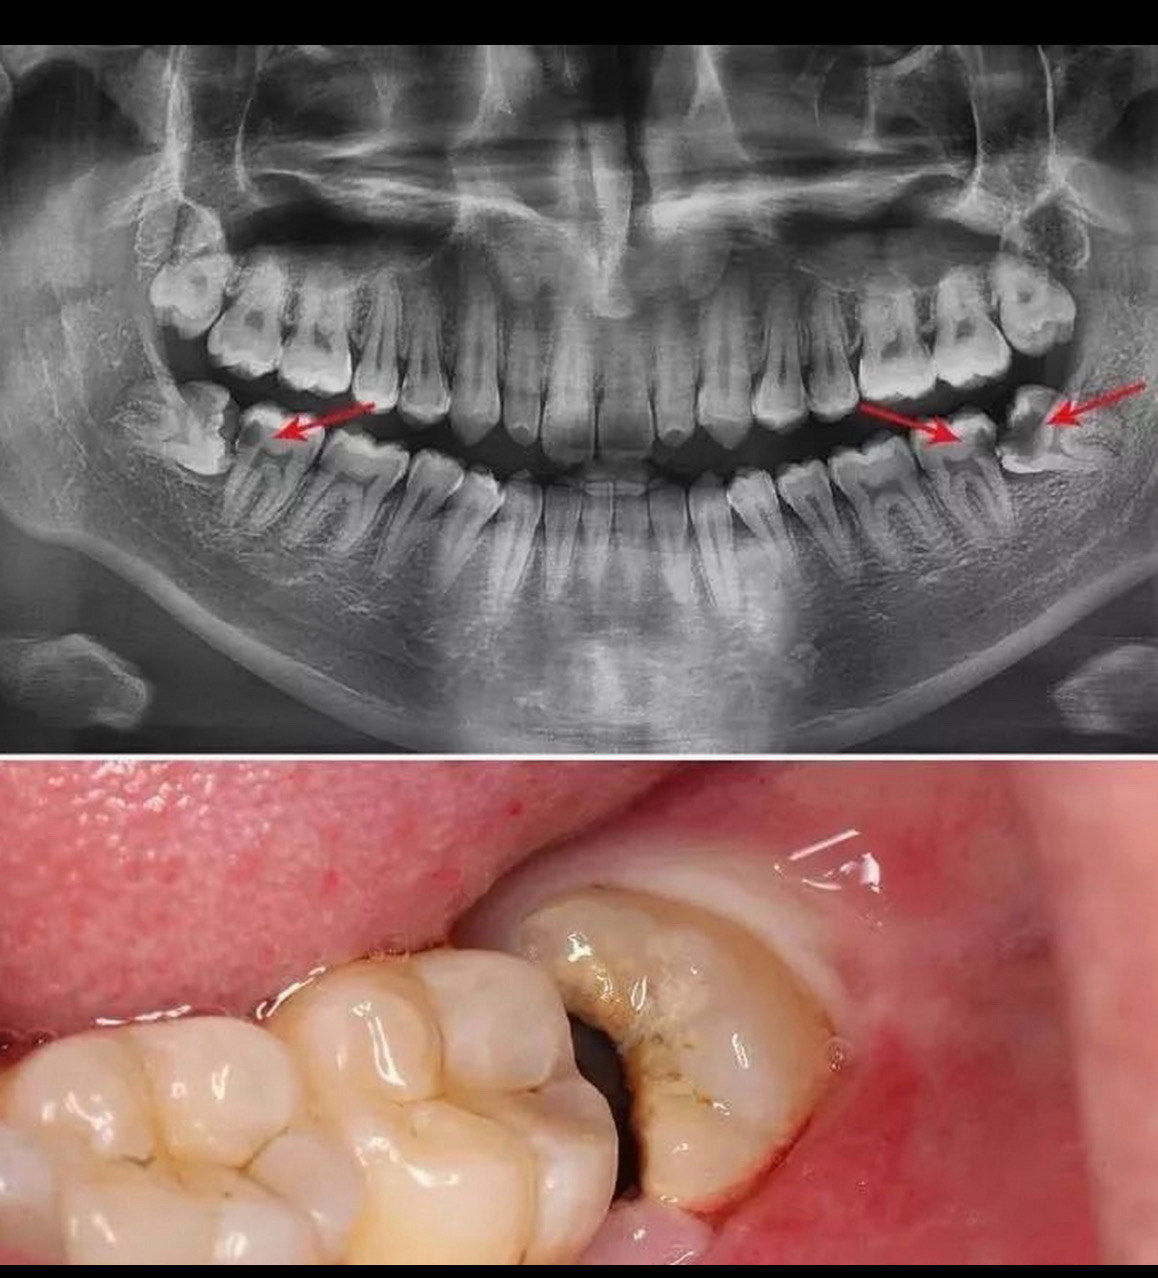

颊舌向阻生智齿拔除1例